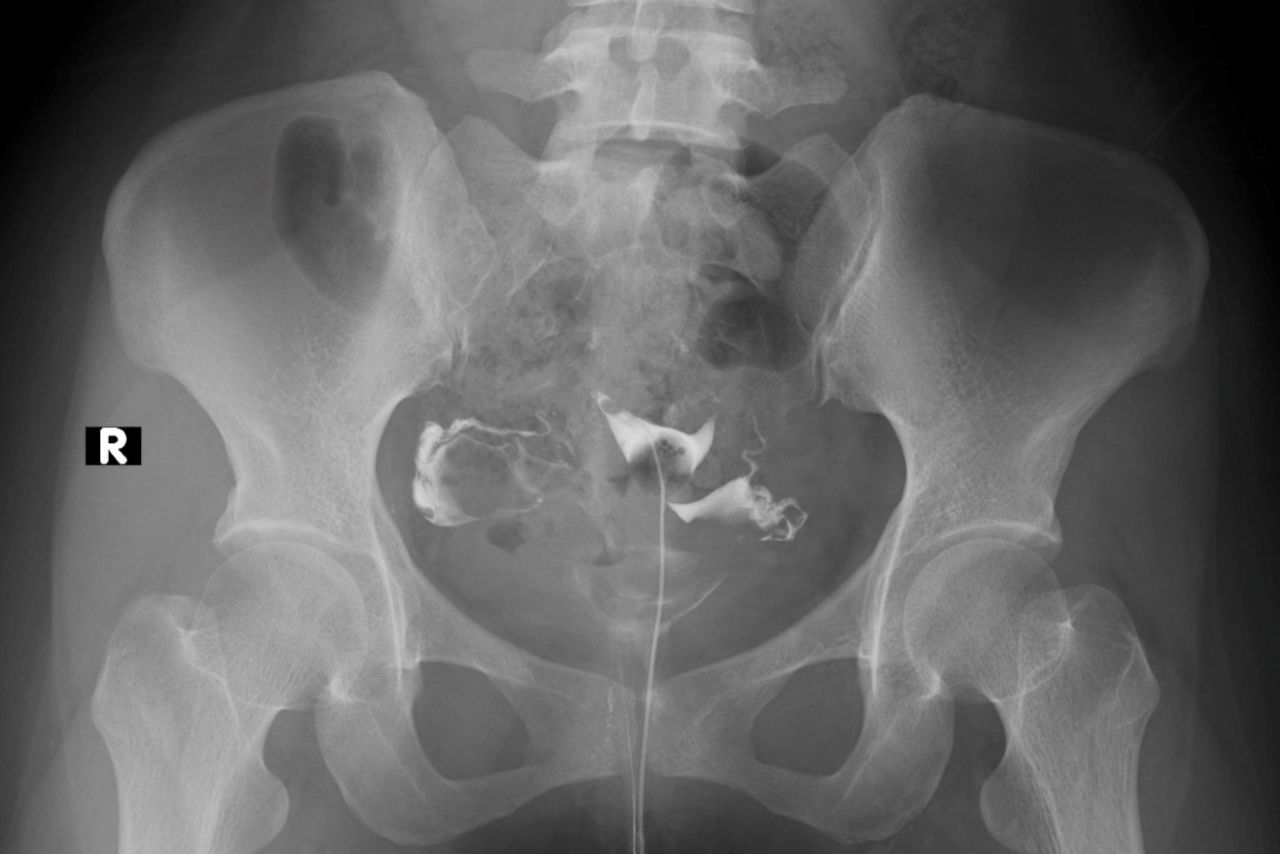

Hysterosalpingography